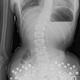

Brianna complained of back pain, and I noticed that her spine was twisted.

Spoke on phone and emailed X-rays. Dr. Pappas said she would be an excellent candidate with approximately 18 degree curve. Based in Chicago with the nearest office in Phoenix, the travel, costs and doctor visits were too financially burdening.

Was told that Brianna had scoliosis and treatment and therapy would be around $5000.00 for the first 3 months.(see posture screening via email)

Was told that Brianna had approximately 12 degree curve and thermal scan and EMG scan was performed as well as various assessments. Weekly adjustments of minimum 2/week was recommended at an affordable rate. Dr. Wise was thorough in his assessment and test in knowledge of pediatric scoliosis. I felt confident for his care with Brianna. (see documents)

Told by Dr. Pappas that the brace was placed on the incorrect side and that her spine had worsened (see phone record and email)